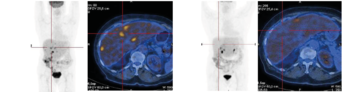

Exemples d’images obtenues par le service de Médecine Nucléaire de l’hôpital de Citadelle

Grâce aux technologies d’imagerie hybride, il est possible de combiner en un seul examen une imagerie fonctionnelle et une imagerie anatomique, améliorant ainsi la précision du diagnostic et le suivi médical.